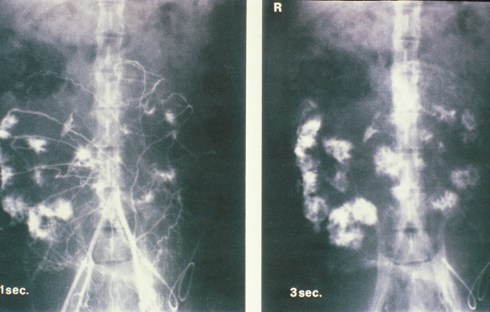

The radiologic injection studies demonstrated that the spiral arteries filled the intervillous space intermittently (Fig 2).

Fig 2: This is an illustration from Drs. Ramsey and Donner’s monograph of radiologic injection into the uterine circulation of the pregnancy monkey. The entire placenta is not circulated but rather separate spiral arteries in this one injection sequence.